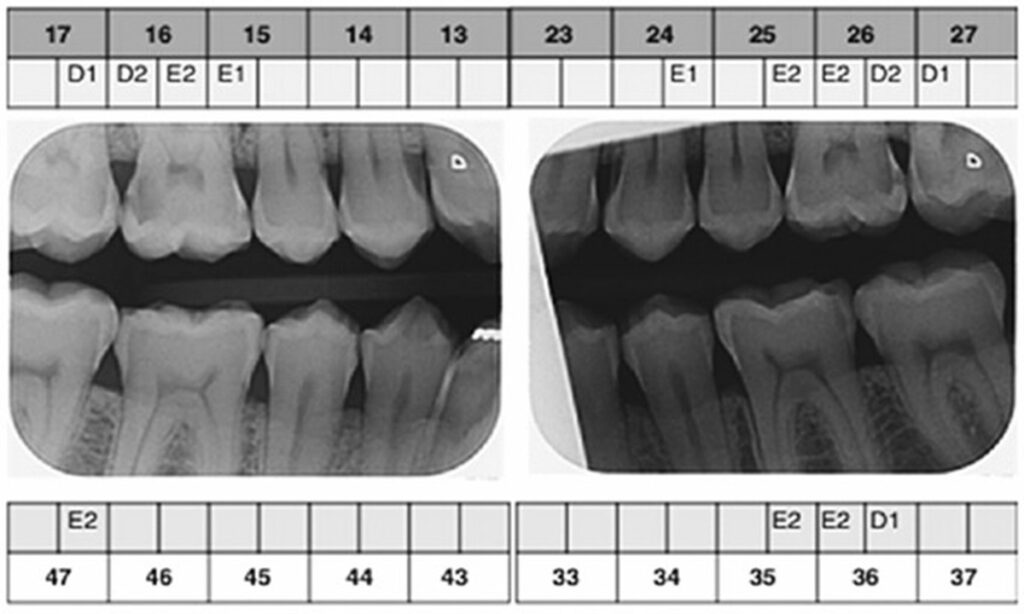

بایت وینگ (Bitewing)

عکس بایت وینگ تصاویری از دندان های فوقانی و تحتانی در یک قسمت کوچک از دهان ارائه می دهد. این نوع رادیوگرافی برای تشخیص پوسیدگی های بین دندانی، سطح جویدن دندان ها و ارتفاع استخوان های اطراف دندان ها بسیار مفید است.